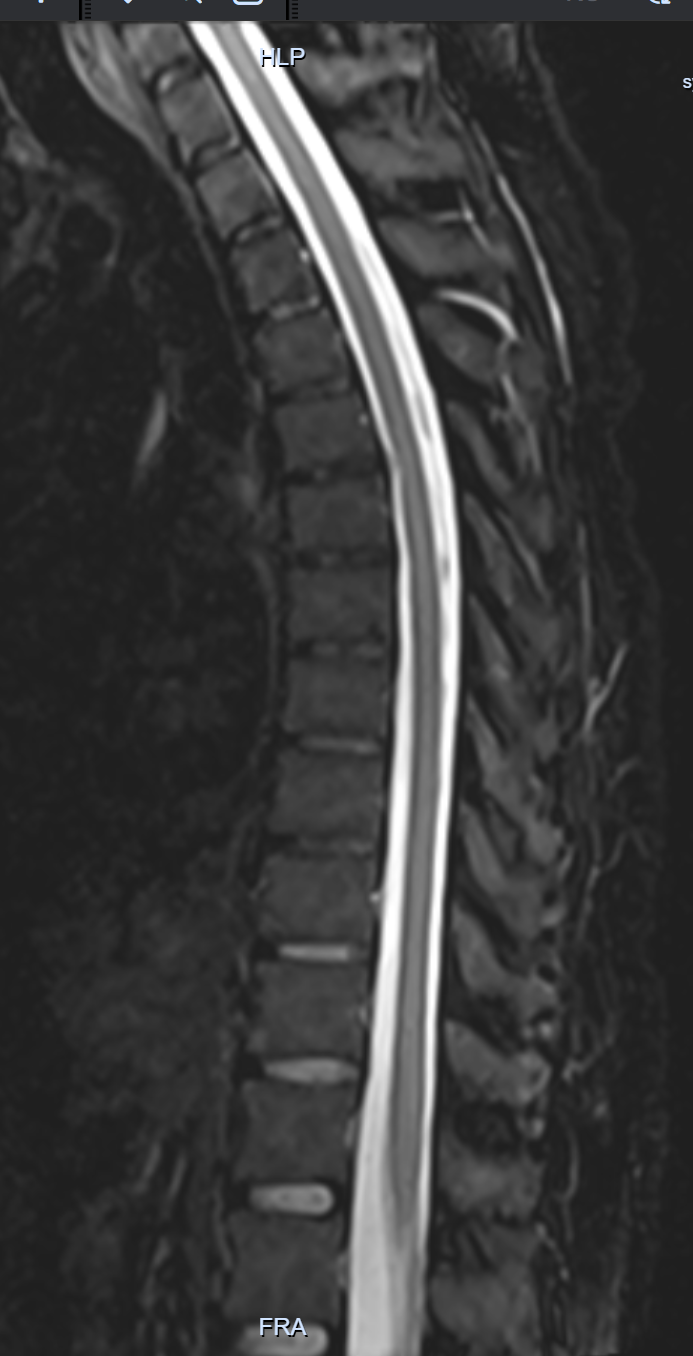

鉴于患者既往病史,首先需要排除动脉夹层复发并累及脊髓供血动脉的可能性,医院迅速开启绿色通道,立即安排主动脉强化CTA检查。

CTA显示:“胸、腹主动脉及双髂动脉粥样硬化

;主动脉弓降部支架术后;主动脉弓降部前方混杂密度灶,考虑假腔机化可能;降主动脉下段附壁血栓可能。请结合临床。”(见图1、图2)

图1

图2

报告并未明确支持新发的、活动的主动脉夹层,尤其是那种足以瞬间阻断多根脊髓根大动脉的广泛撕裂。同时,颅脑CT也未见急性出血或大面积梗死。